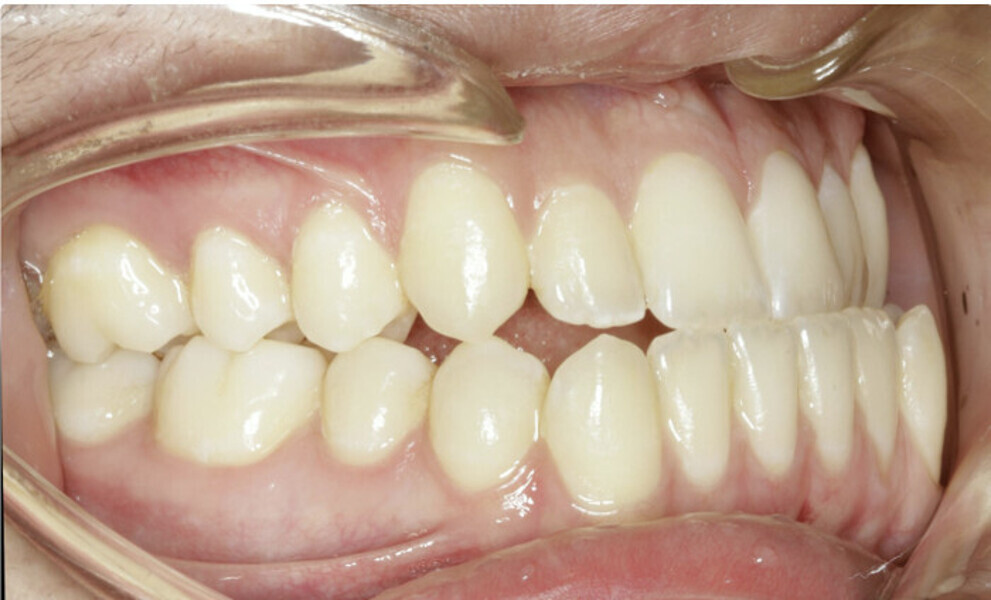

New Age orthodontics and orthopaedics with temporary anchorage devices